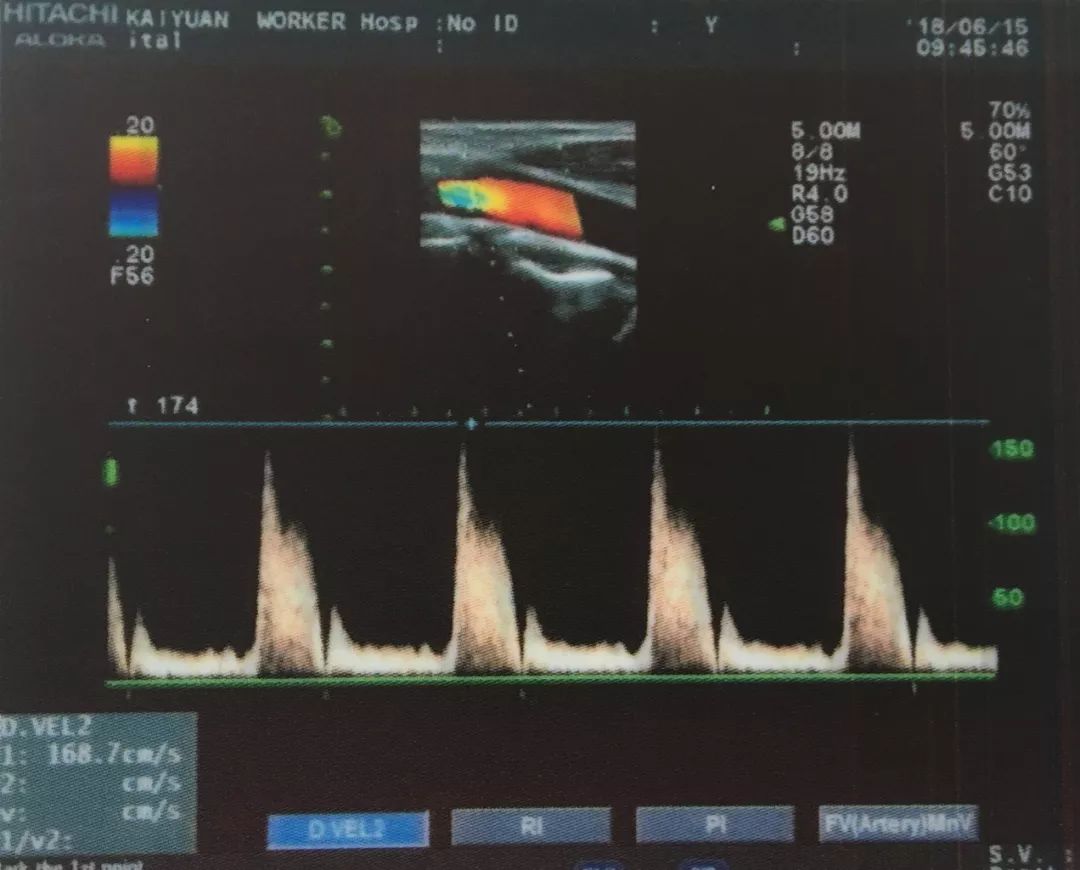

今年60岁的杨进聪,突然出现右侧肢体活动不灵,并伴有言语不清的症状。其从砚山县城迅速赶到开远工人医院就医,入院后,紫主任立即对他进行了颈部血管超声检查,发现其双侧颈总动脉粥样斑块形成(混合斑);右侧颈内动脉狭窄;左侧颈内动脉重度狭窄,甚至闭塞声像图;狭窄段收缩峰值明显增高,远端血流频谱呈“小慢波”。

杨进聪住院期间,紫主任对其进行了DSA全脑血管+主动脉弓造影检查,明确诊断为:1、左侧颈内动脉次全闭塞。2、右侧颈内动脉起始段中度狭窄。DSA与超声结论高度吻合。